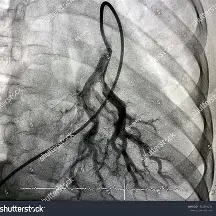

Gold standard diagnostics for PE?

CT Pulmonary Angiography

Use VQ scan (Ventilation/Perfusion scan) if contrast contraindicated

Surgical Procedures for PE: (3)

1. IVC Filter: (basically filters bloodstream)

• device placed in Vena Cava to trap emboli and prevent PE (option if anticoag isn’t possible)